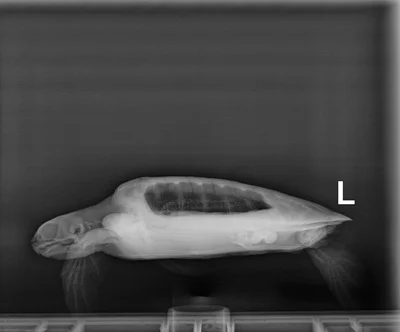

3.2 lbs. non-FP juvenile green

Minor abrasions on carapace, moderate abrasions on plastron

In-house PCV = 26%, TP = 3.2 g/dl, glucose = 113. Started on Ceftazidime, Vit B Complex, and Normosol.